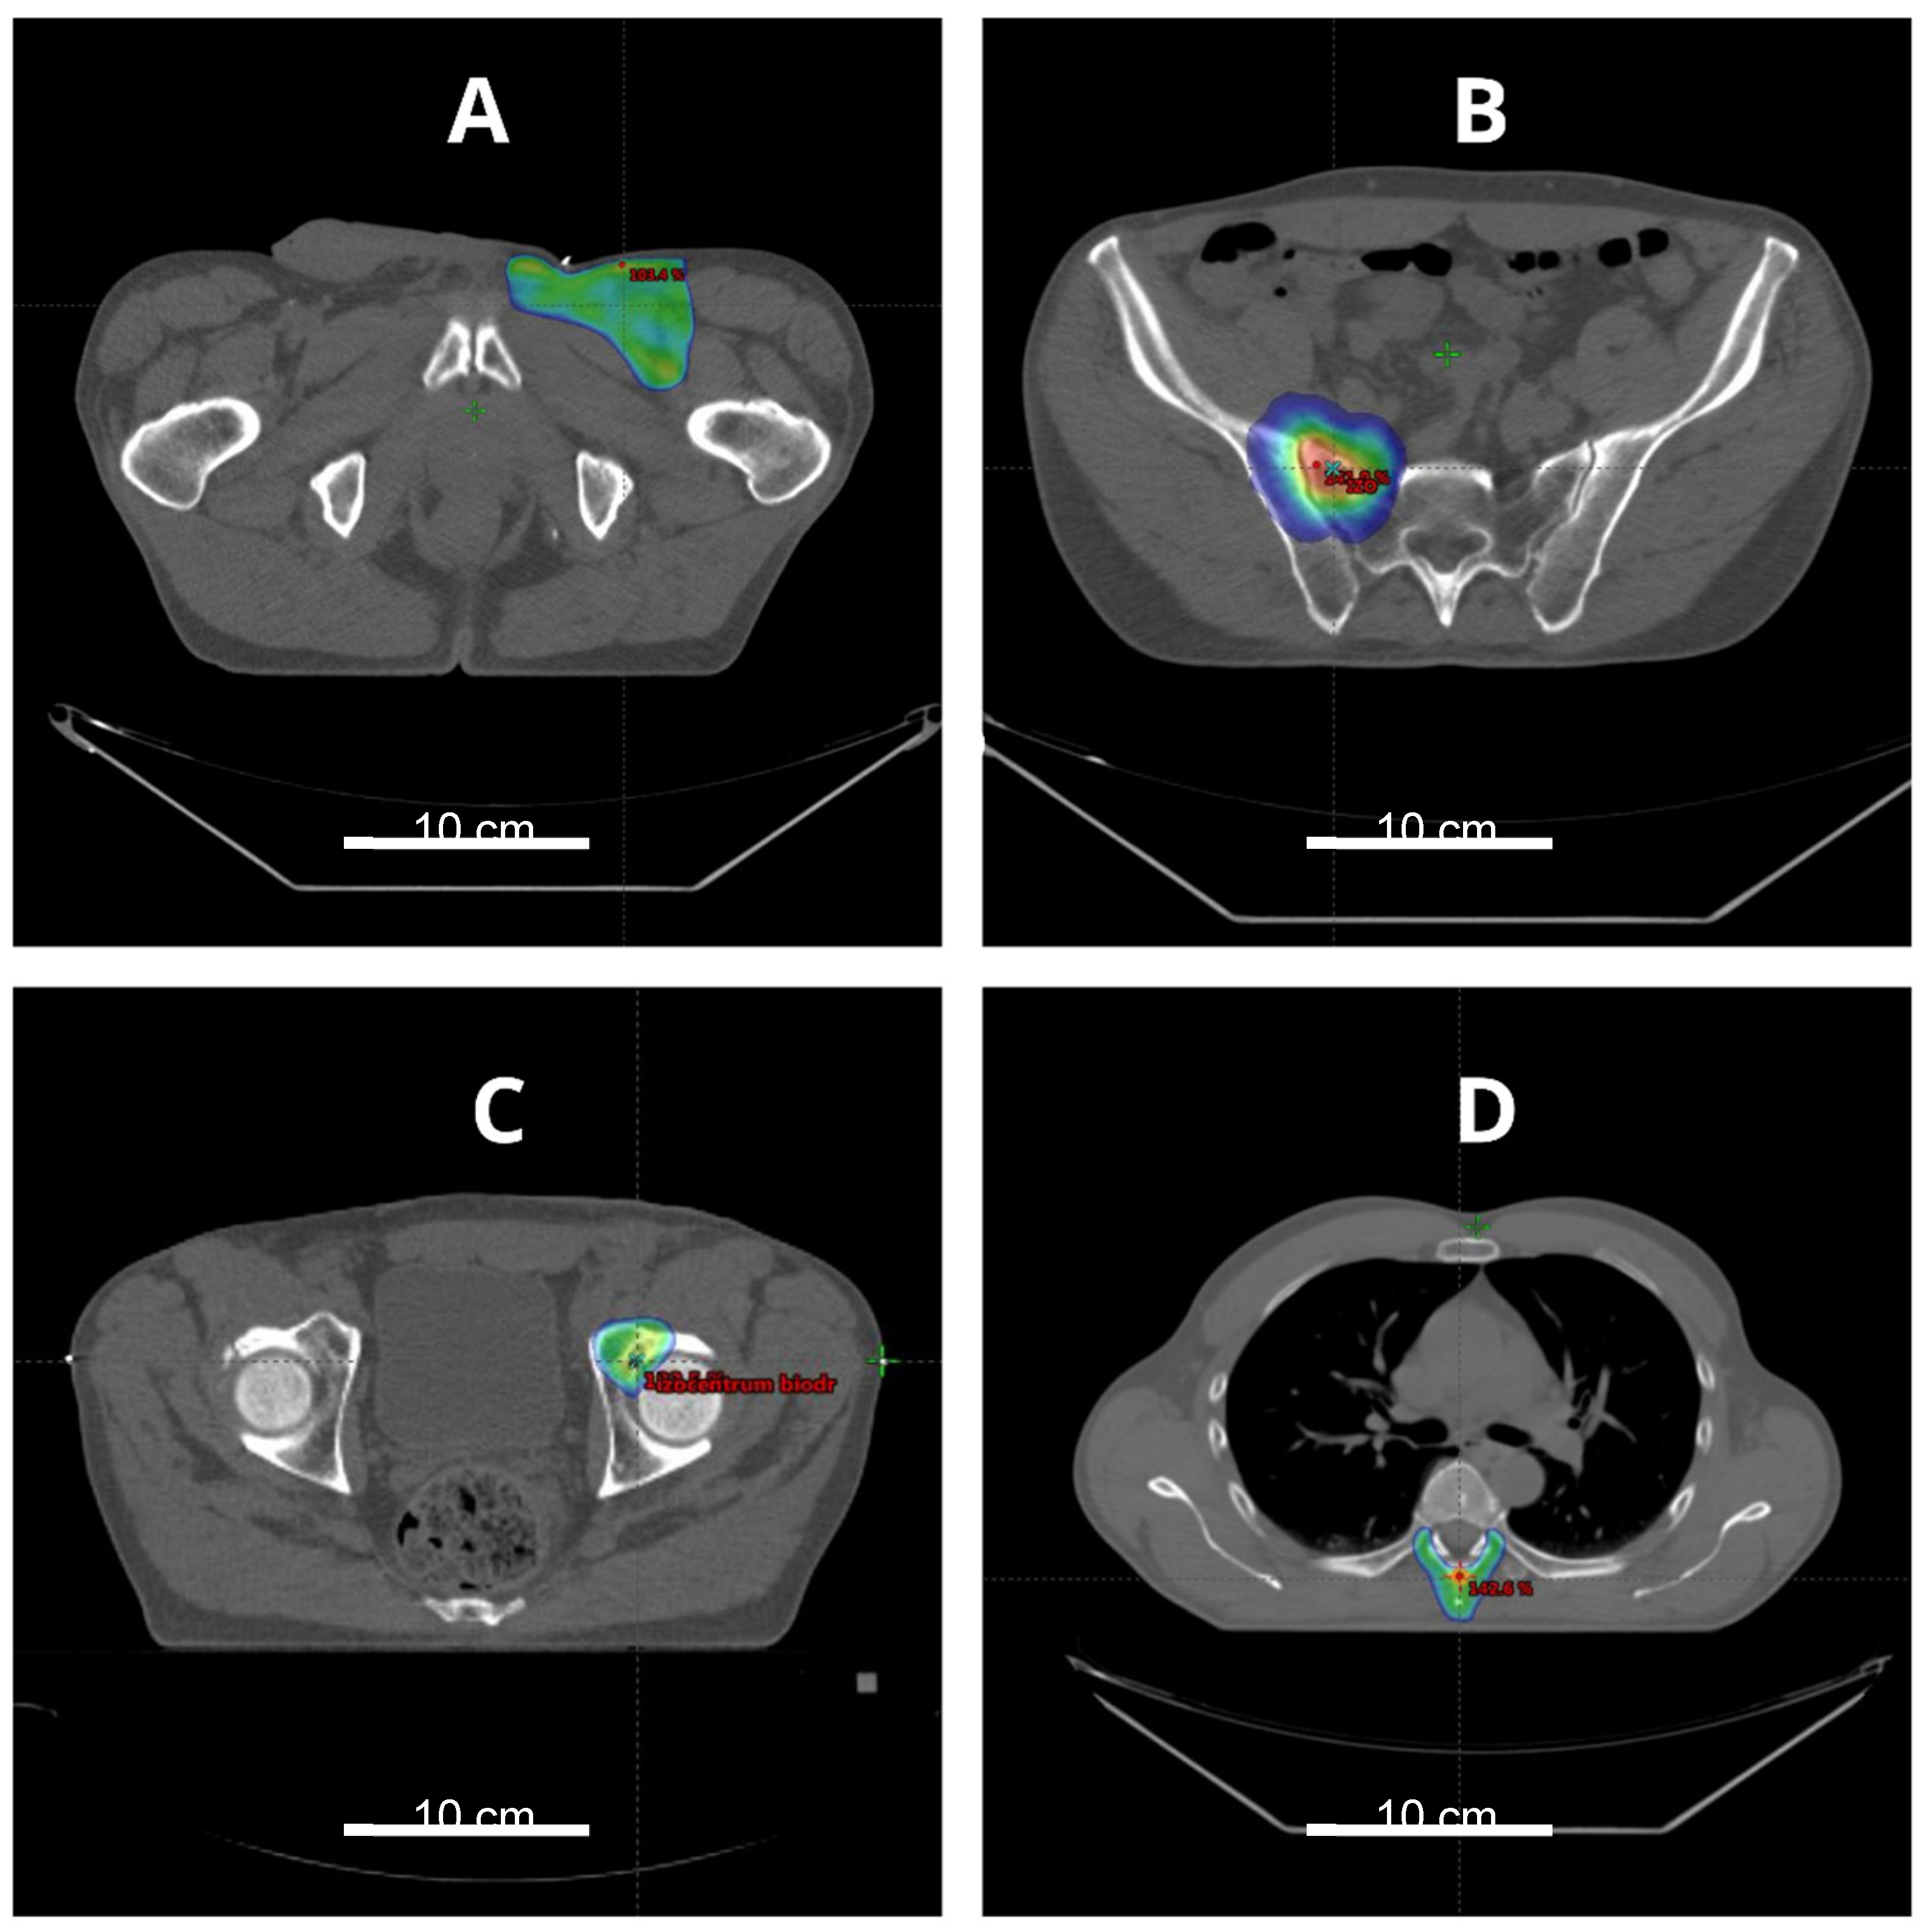

5.1. Radiotherapy of the Primary Tumor

5.2. Radiotherapy of Recurrent Disease